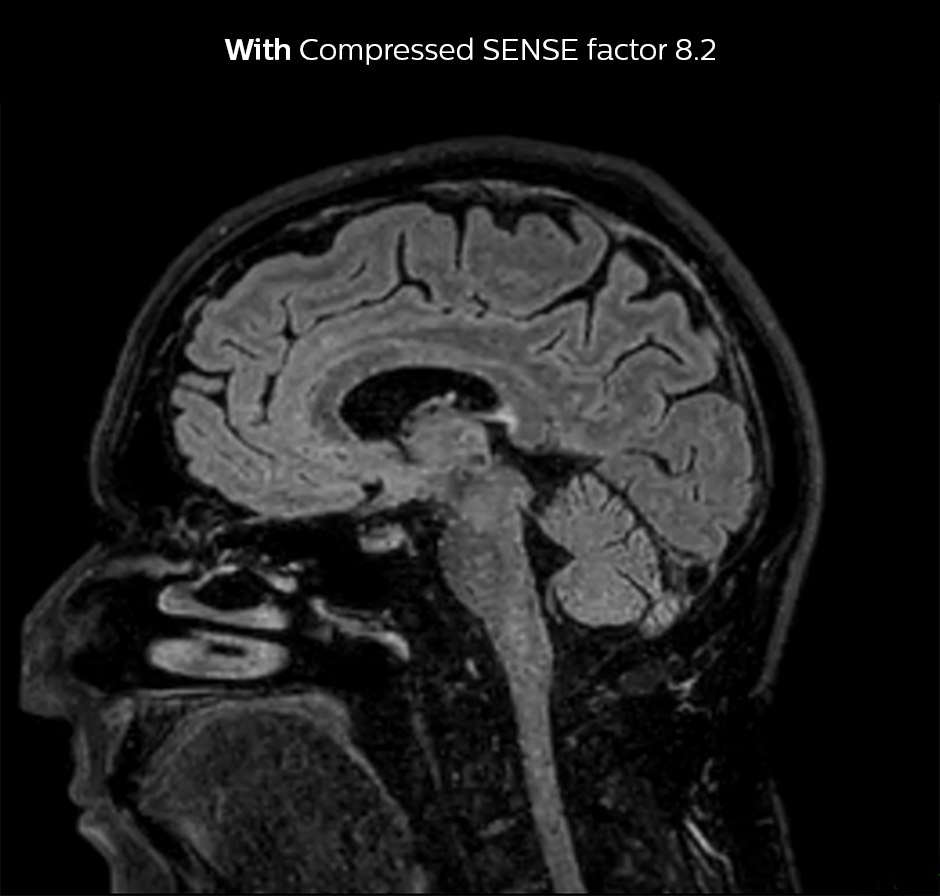

Shorter scan time in brain

Compressed SENSE allows 28% shorter scan time with the same spatial resolution.

3D FLAIR brain WITHOUT Compressed SENSE

3D FLAIR, scan time 5:02 min, voxel size 1.1 x 1.1 x 1.1 mm, Ingenia 1.5T.

3D FLAIR brain Compressed SENSE factor8

3D FLAIR, scan time 3:36 min, voxel size 1.1 x 1.1 x 1.1 mm, Ingenia 1.5T.

Dr. Sartoretti remembers how Compressed SENSE immediately impressed her in the first scans. “Our first sequence with Compressed SENSE was a 3D FLAIR in the brain on the Ingenia 1.5T, where we used a Compressed SENSE factor of 8.2. Then we tried a 3D TSE mDIXON post-contrast sequence with a CS factor of 7. In both cases the quality was really good.”